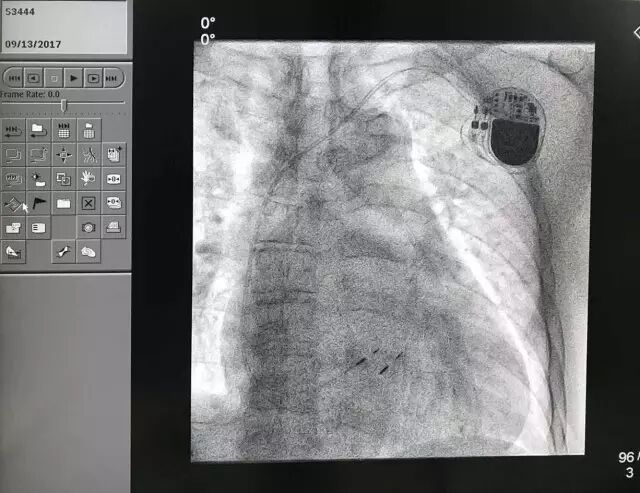

9月13日,云南博亚医院成功完成云南省首例希氏束起搏手术,跻身国内少数有能力实施此类手术的医院行列,为即将成立的博亚医院•哈特瑞姆心律失常诊疗中心奏响了开诊序曲。

哈特瑞姆心脏医生集团核心专家、哈尔滨医科大学第二医院李述峰教授、云南博亚医院吕云院长、翟菁主任等参与了手术。

患者是一名79岁的男性病人,长程持续性房颤伴二度房室阻滞,平均室率52bpm,双房巨大,而且右心衰,双下肢浮肿、消瘦。

因为心动过缓,患者需要心室起搏支持,而常规心室起搏破坏心室收缩同步性,会令原本存在的心衰加重,因此考虑施行希氏束起搏,以达到最佳的生理性起搏。

与此同时,因患者双房显著扩大,转复房颤不可行,拟视起搏后药物控制情况决定是否进行房室结消融以保证完全规则的心室律。

手术大约2小时,过程非常顺利,获得希氏束起搏阈值0.75V/0.5ms。心室后备起搏参数0.5V/0.5ms。事实证明,希氏束起搏和之前预测的一样,达到了非常理想、而且是疗效最佳的结果。